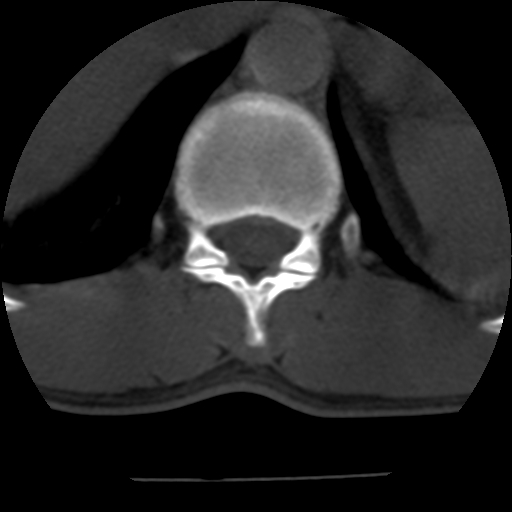

男,31岁,从6米高处坠落伤两天,腰背部疼痛,临床要求ct扫描胸10-腰1。请大家帮忙看看骨质有问题吗?

t12、l1锥体前缘轻度楔形变,平扫示椎体前缘骨小梁欠规整,第9幅图示椎体前缘骨质不连续,结合外伤史考虑椎体轻度压缩骨折。

楼主扫描层厚可能较大,每个椎体只有三个层面.

从所示层面分析,无明确骨折征象,象类似病人我个人会建议mri除外骨挫伤.

从上查骨窗第九片椎体前缘皮质显示断裂.压缩骨折?